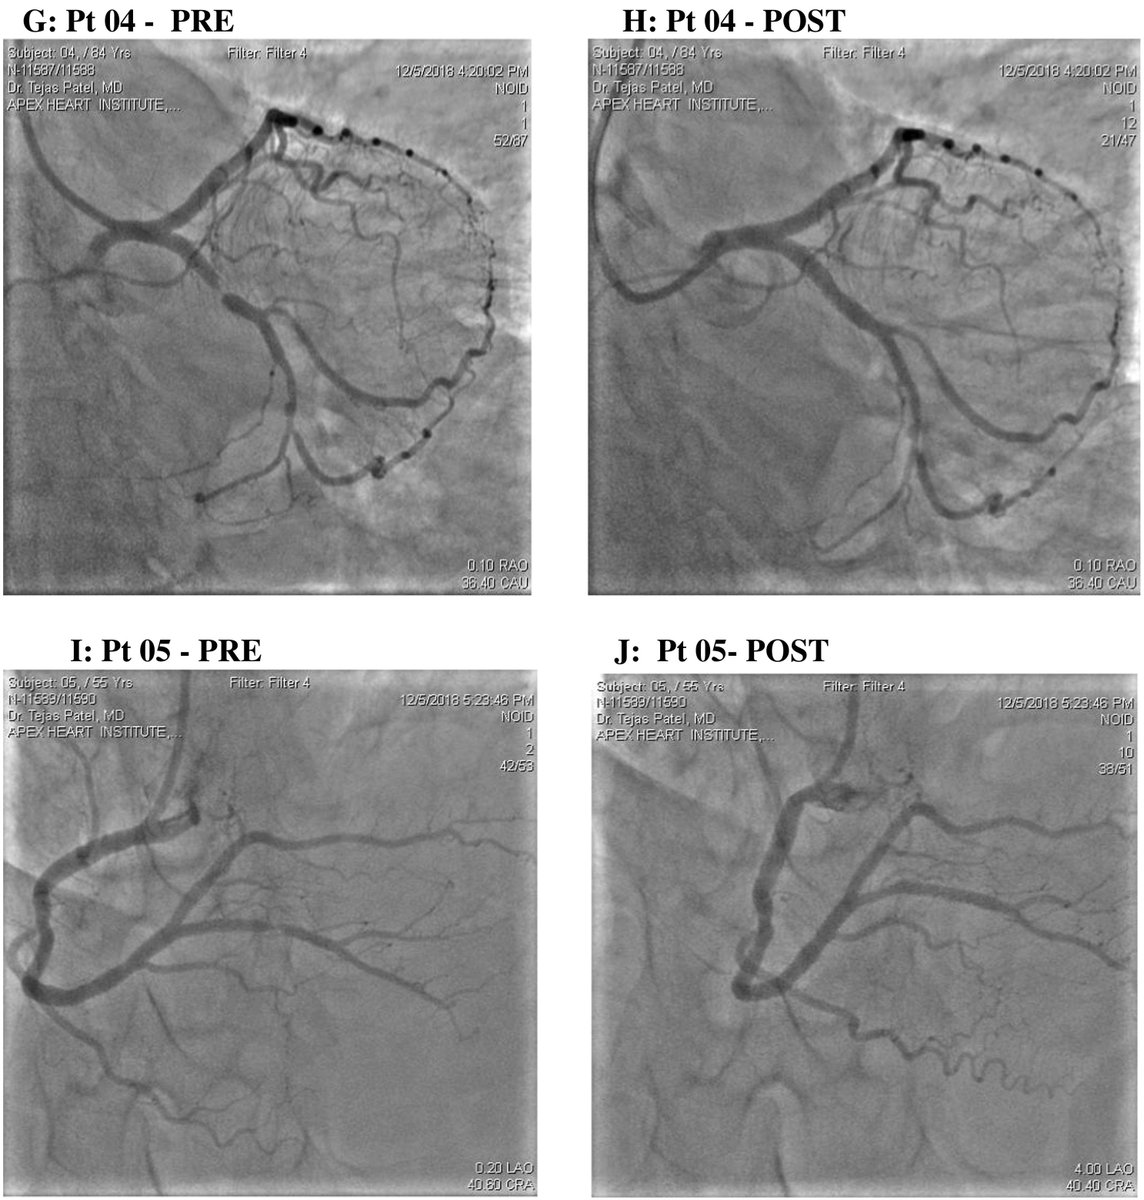

Do not miss our latest research on #Robotic -assisted percutaneous coronary intervention in patients with #CoronaryArteryDisease @DrTejasPatel1 @DrSanjayCShah @samirpancholy @apex_heart #openaccess #heart

https://t.co/H2I1u9HJrB

We are in the #Lancet! A rewarding journey. #telerobotic PCI being developed by #Corindus is going to be the future of #coronary intervention and distant #stroke management. My team @apex_heart is excited!

Long Distance Tele-Robotic-Assisted Percutaneous Coronary Intervention: A Report of First-in-Human Experience

ONLINE FIRST: Long Distance Tele- #robotic -Assisted Percutaneous Coronary #intervention : A Report of Fist-in-Human Experience @DrTejasPatel1 @DrSanjayCShah @samirpancholy @apex_heart @EClinicalMed #CoronaryArteryDisease #intervention Full text -> https://t.co/WL59hn77TM